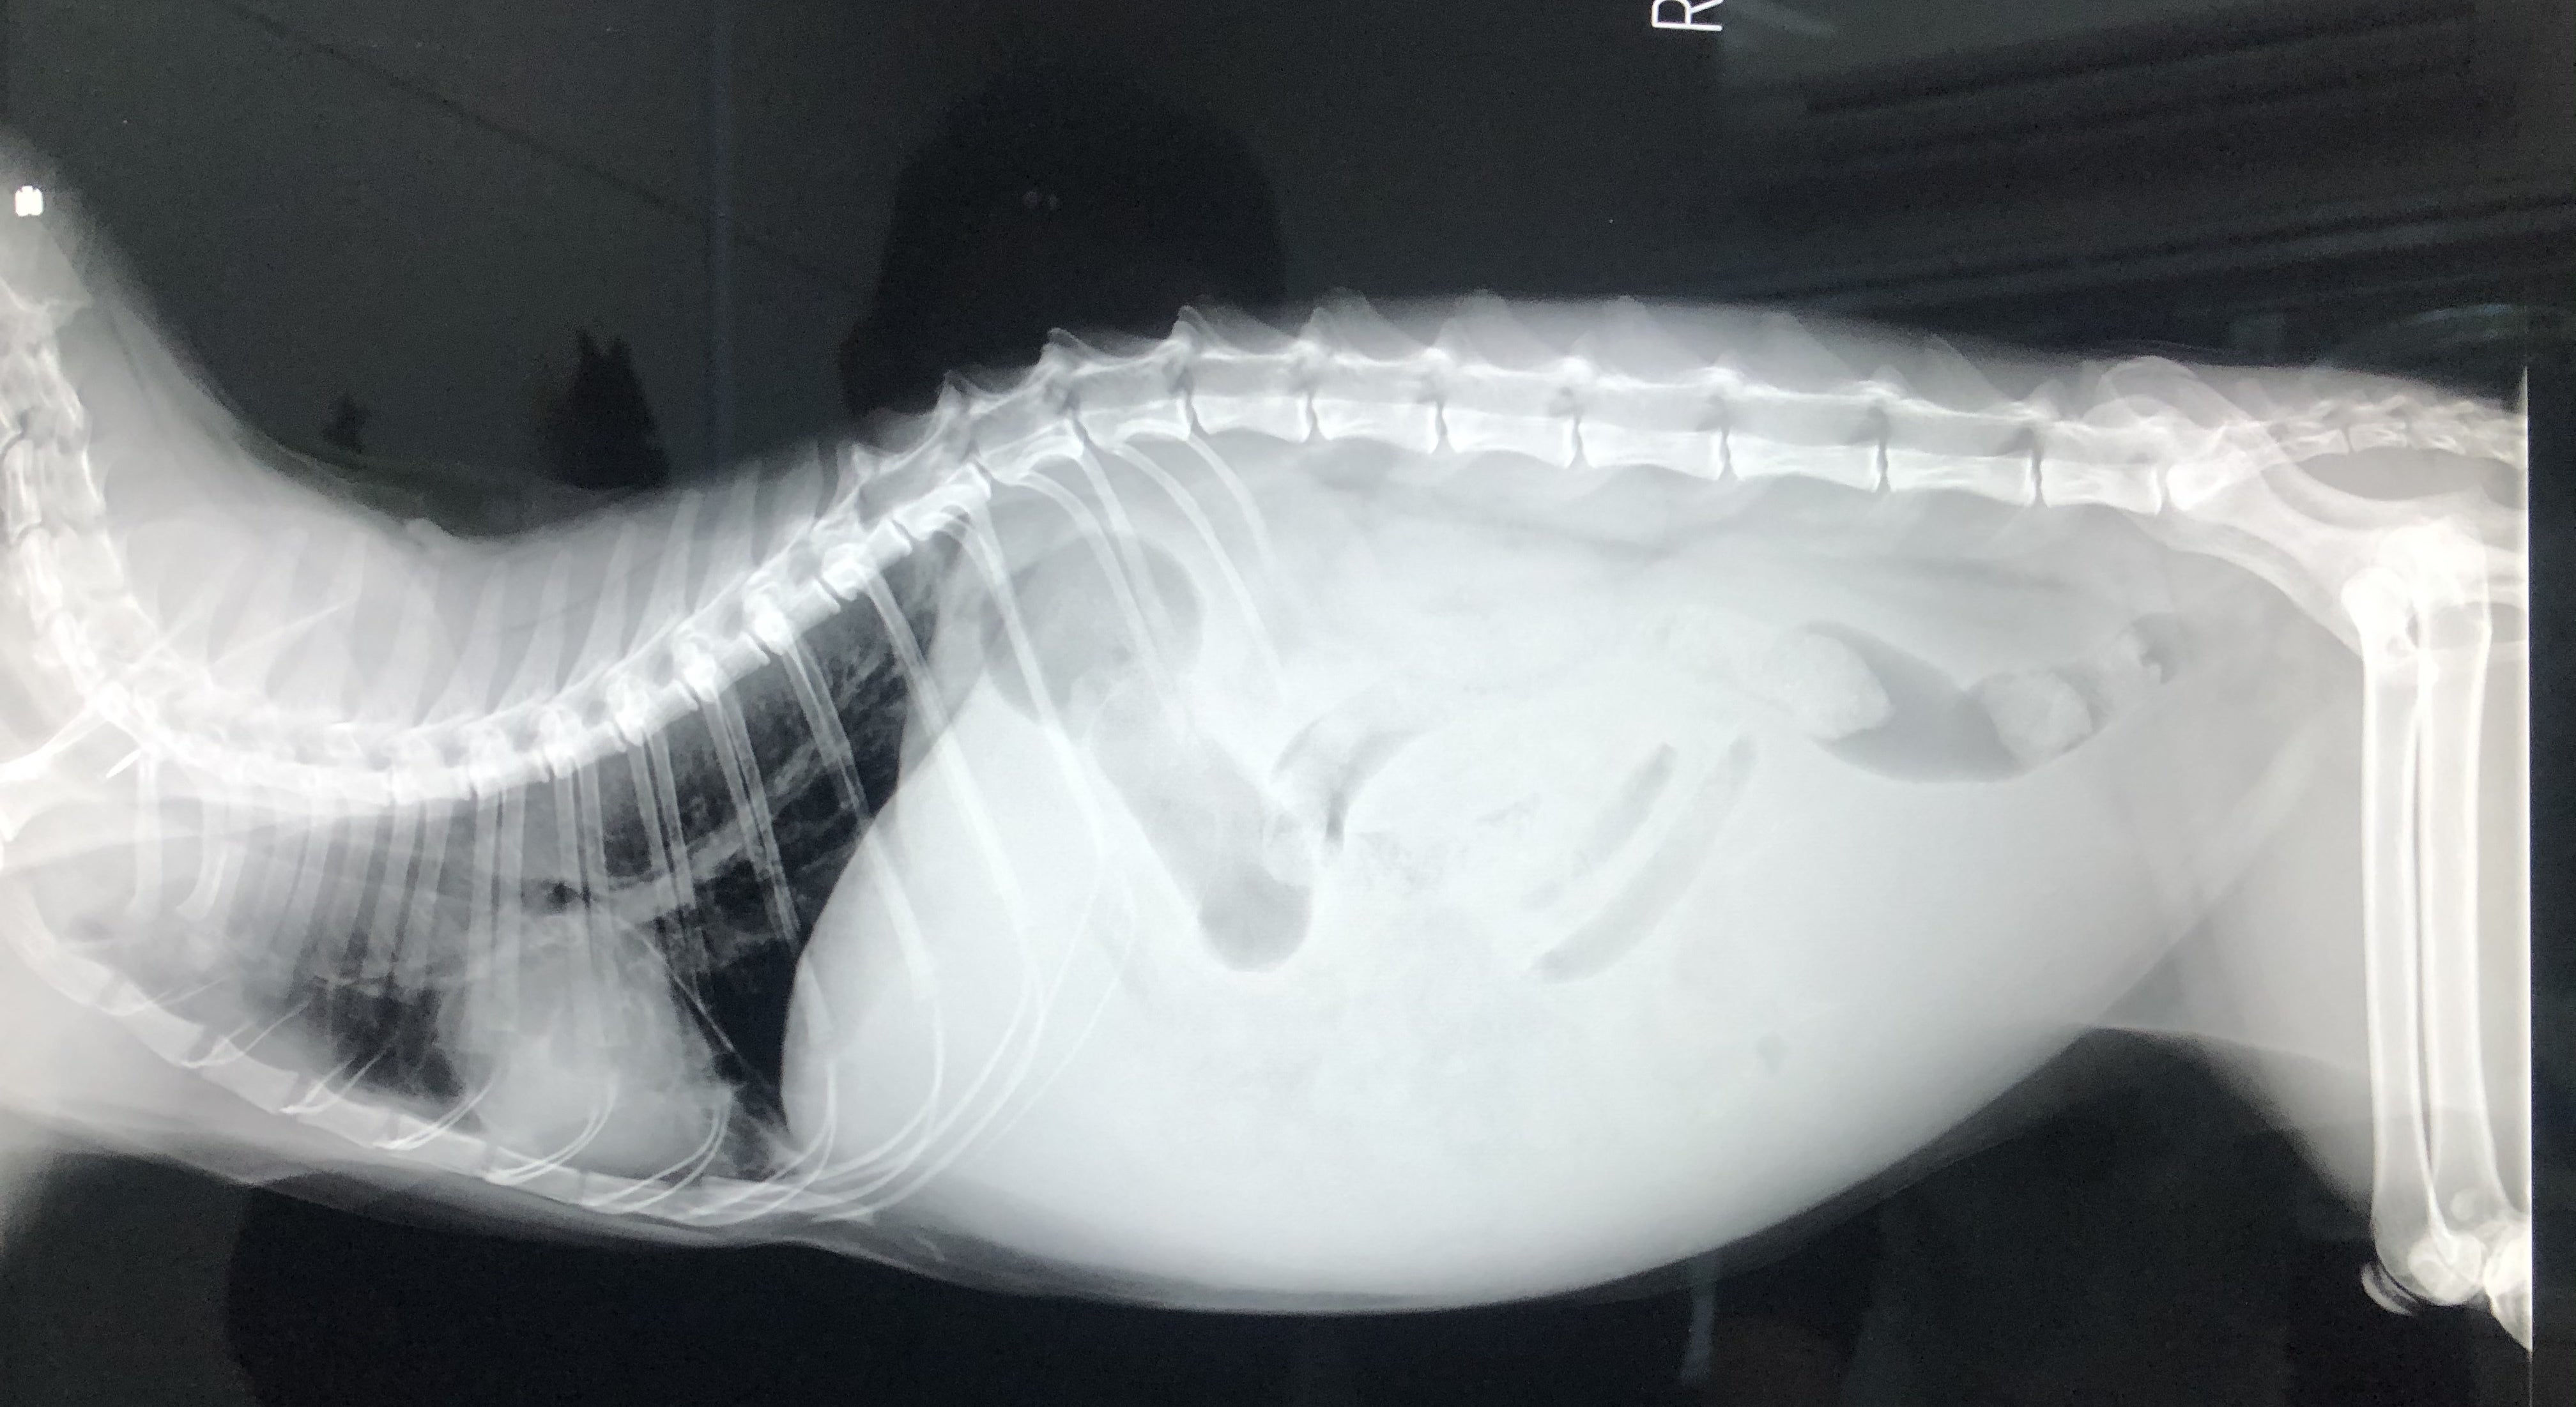

昨年6月の第一子の誕生の前に、ずら丸を家に迎え入れました。娘とも仲良く過ごしていましたが、突然のFIP疑診。ウェットタイプで腹水が溜まってしまい、まともに生活を送るのが困難な状態になってしまいました。今回の診断を機にこのプロジェクトを立ち上げています。

FIPという診断を受けた時に、あらゆる手段を使いこの病気について調べました。動物病院の先生やネットで調べた結果、外猫・野良猫のほとんどが持っているコロナウイルスが突然体内で変異し、FIPウイルスになるということが分かりました。FIPウイルスは一度発症してしまうと元に戻ることはありません。原因はストレスのことが多いと言われており、ずら丸にストレスを与えてしまっていたと日々嘆くばかりです。現在の症状としては腹水・胸水の貯留、食欲減退、便秘、黄疸、脱水症状です。動物病院への通院で脱水症状については収まりを見せていますが、その他は改善の兆しが見えてきません。

ずら丸の腹水が溜まっているのを見た際、リンパ癌や心臓の病気など様々な病気を疑いました。しかし考えていたよりも状況は重く、不治の病と言われるFIPでした。世界中にFIPで苦しんでいる猫、オーナー様はいらっしゃいます。MUTIANの治療で完治し、1つの道しるべとすることが出来れば、FIPの診断で悲しむ方は減るのではないかと思います。